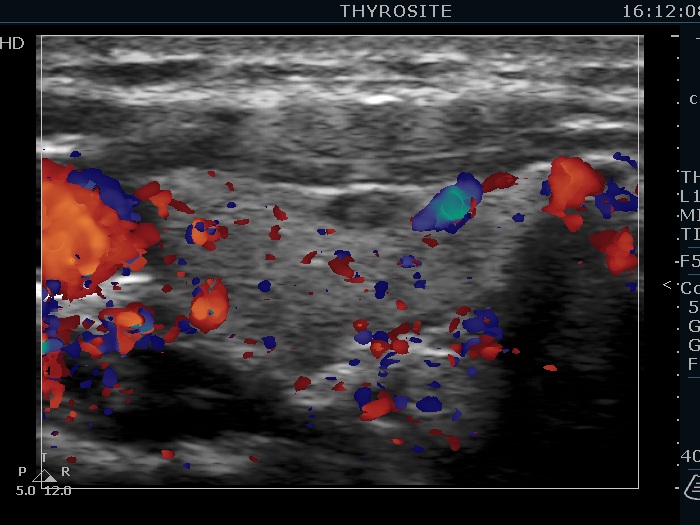

Ultrasonography. The thyroid was echonormal. There were several hypoechoic nodules in the left lobe. The middle one had back wall cystic figures. There were 3 or four discrete, deeply hypoechoic lesions above and lateral to the left lobe in the neck. One of them presented with a hilum-like figure while the others lacked hilum.

Aspiration cytology of the lesion in the middle part of the left lobe resulted in benign lesion. One of the masses in the neck was also aspirated and a heterogeneous lymphoid cell population was gained. Wash-out thyroglobulin resulted in 13 ng/mL, while serum thyroglobulin was 19.4 ng/mL.

The lymph nodes had a non-typical presentation. They lacked a regular hilum.